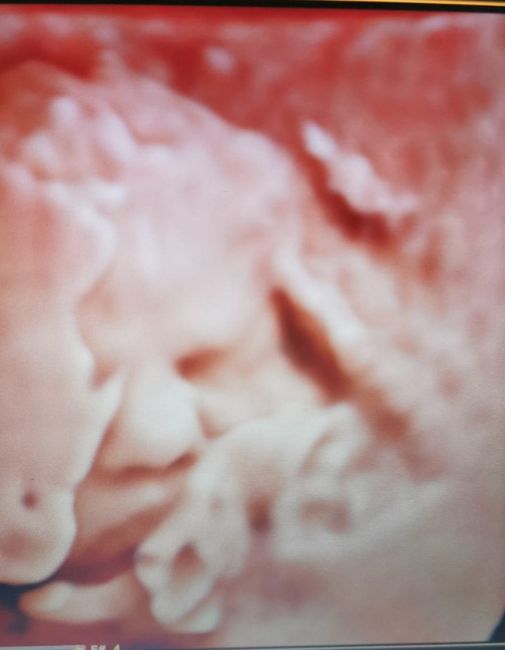

Future mamme Agosto 2021!Da Miry , Il 8 Luglio 2021 alle 14:18

Ciao a tutte! ...